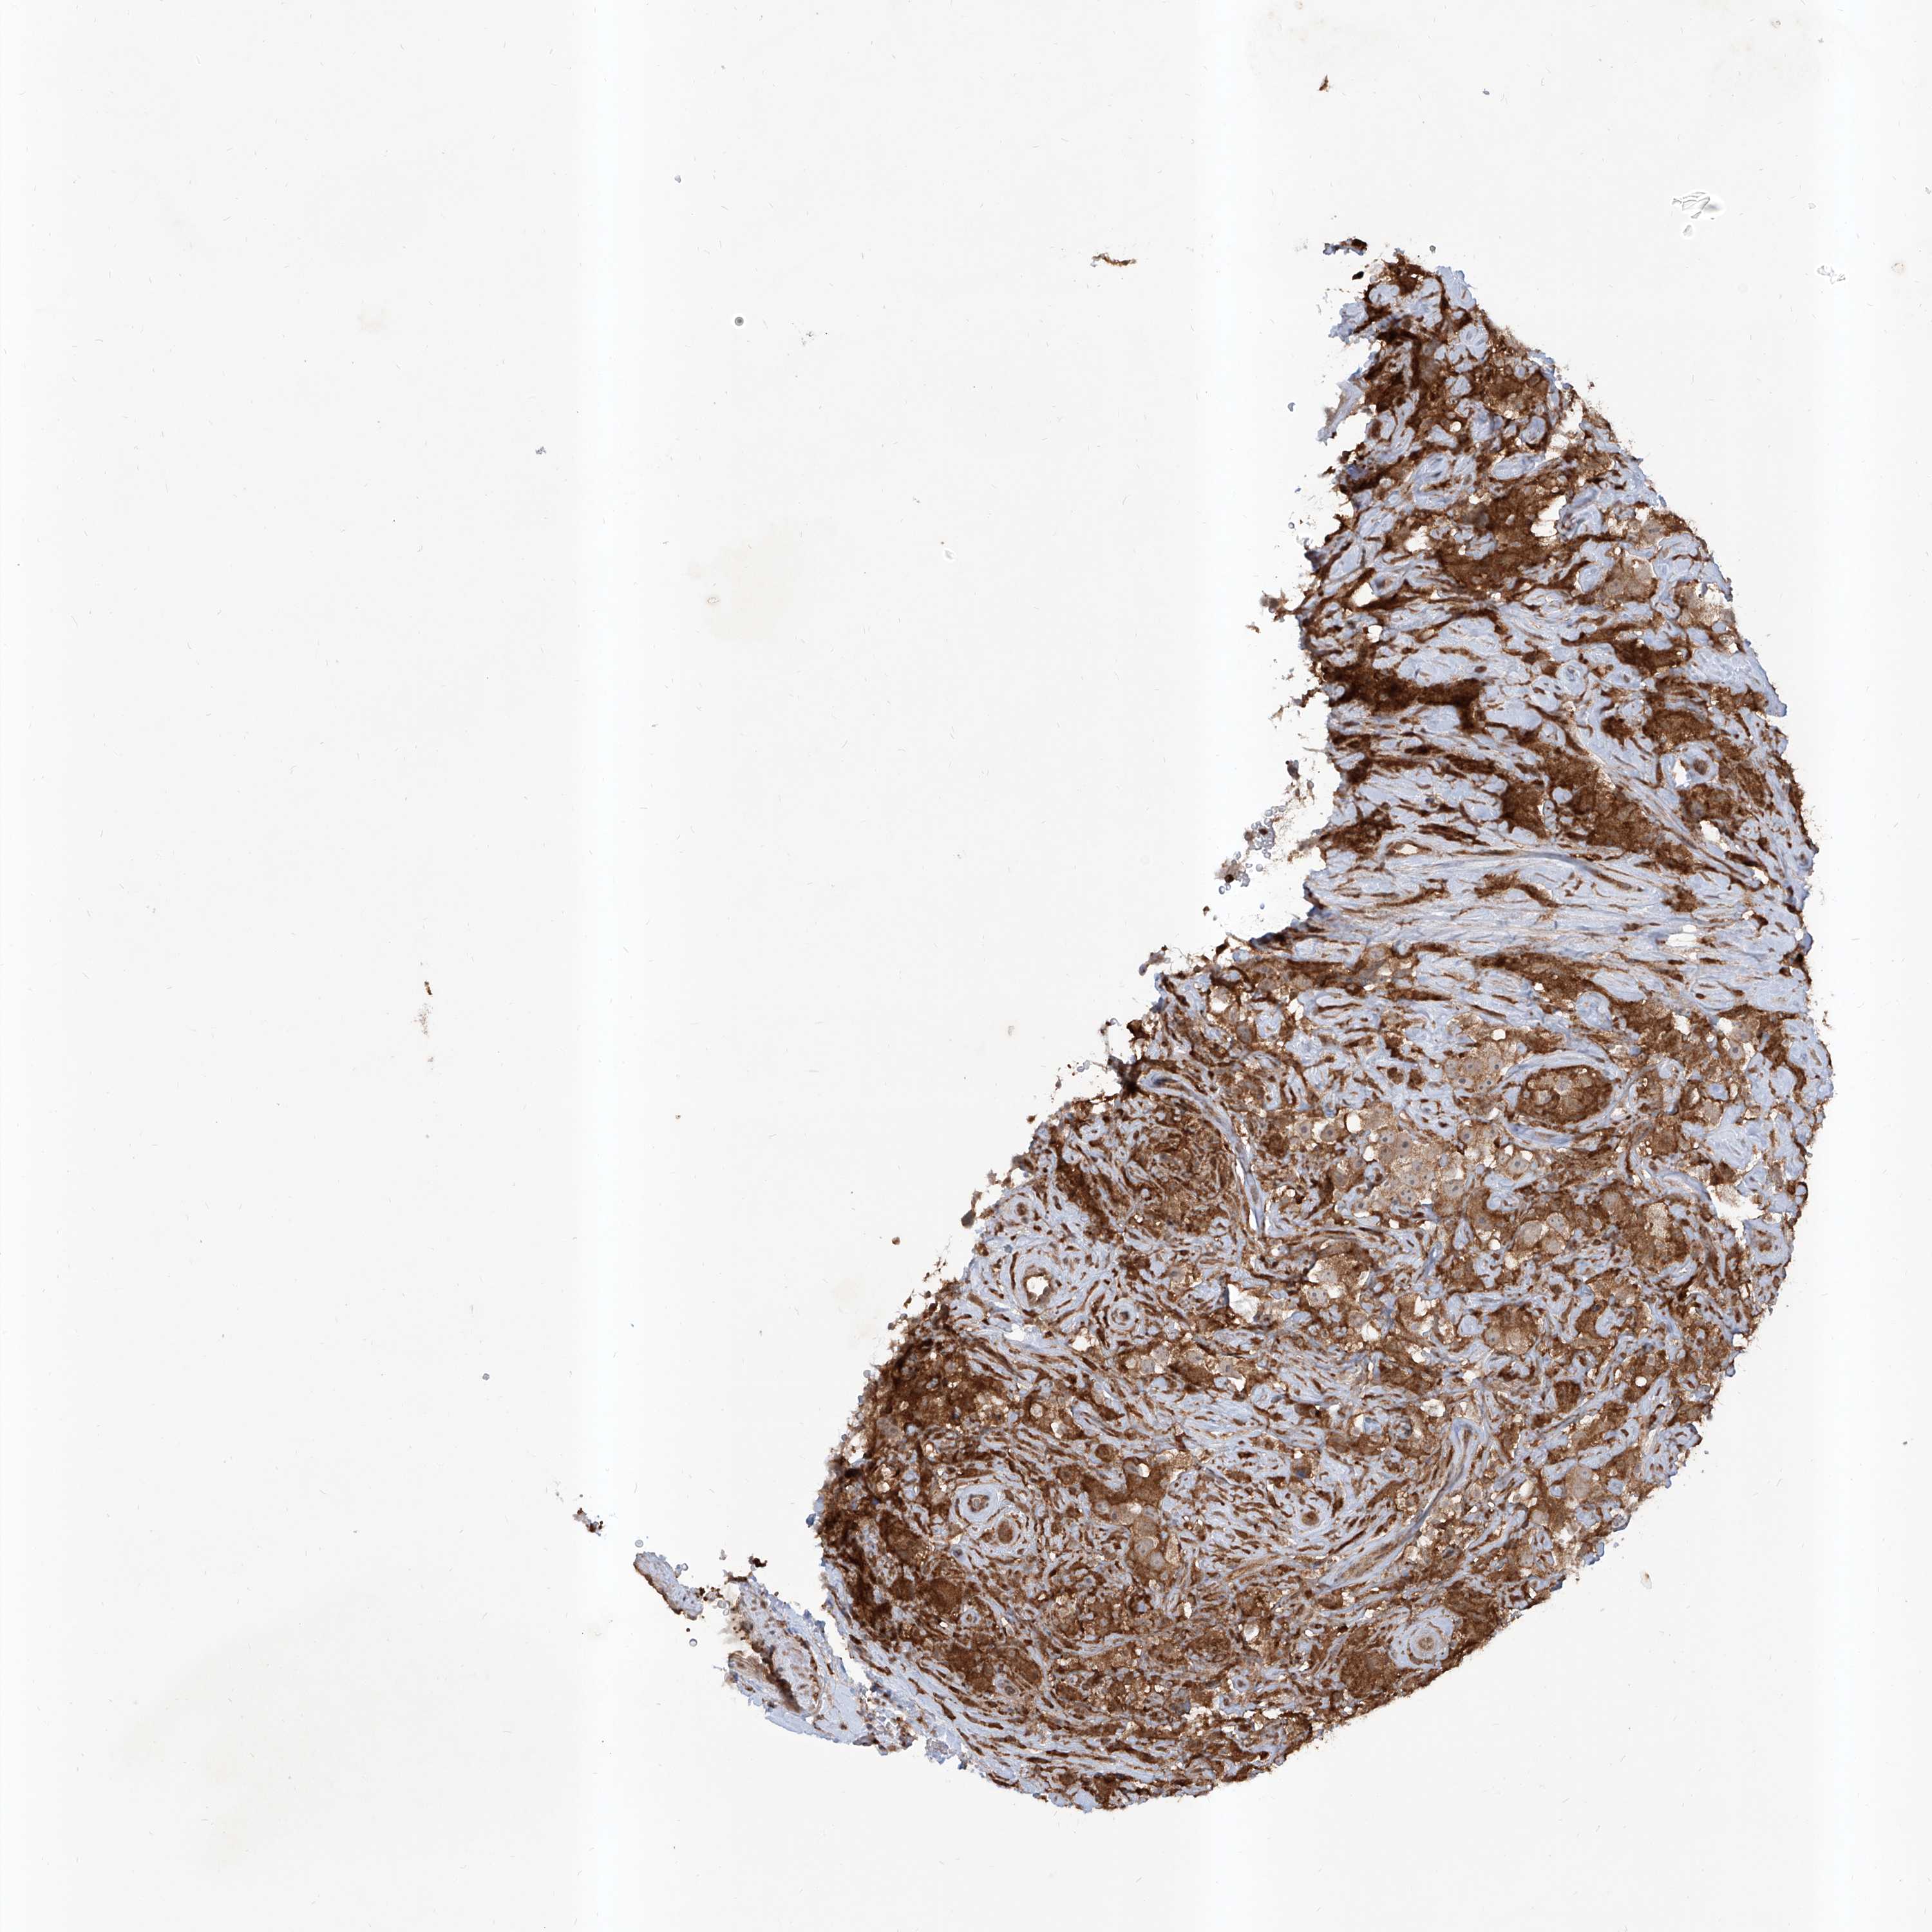

TESTIS CANCER - Protein expressioni

A mouse-over function shows sample information and annotation data. Click on an image to view it in a full screen mode. Samples can be filtered based on level of antibody staining by selecting one or several of the following categories: high, medium, low and not detected. The assay and annotation is described here.

Note that samples used for immunohistochemistry by the Human Protein Atlas do not correspond to samples in the TCGA dataset.

Antibody stainingi

Antibody staining in the annotated cell types in the current human tissue is reported as not detected, low, medium, or high, based on conventional immunohistochemistry profiling in selected tissues. This score is based on the combination of the staining intensity and fraction of stained cells.

Each image is clickable and will lead to virtual microscopy that enables deeper exploration of all samples and also displays staining intensity scores, fraction scores and subcellular localization as well as patient and tissue information for each sample.

Antibody HPA028911

Antibody CAB037020

Staining

High

Medium

Low

Not detected

Intensity

Strong

Moderate

Weak

Negative

Quantity

>75%

75%-25%

<25%

None

Location

Nuclear

Cytoplasmic/membranous

Cytoplasmic/membranous,nuclear

Urothelial carcinoma, High grade

Seminoma, NOS

Carcinoma, Embryonal, NOS